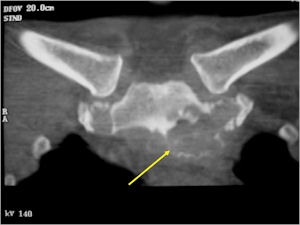

CT Scan:

- More useful for detecting mineralization and evaluating extent of bone destruction than plain X-ray

- The periosteum remains intact around the soft tissue component. Might need a CT scan to detect the subtle calcification (Egg Shell Rim of Calcification) associated with an intact periosteal reaction

- The lesion may be entirely radiolucent but usually shows some degree of mineralization. Mineralization may appear stippled like cartilage but do not see chondroid pathologically. Mineralization is sometimes better detected on a CT scan rather than an x-ray.